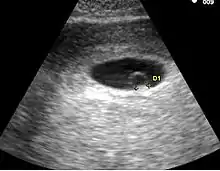

- Le premier signe échographique d'une grossesse est la visualisation d'un sac ovulaire. Il est visible entre 4 semaines et 1 jour et 4 semaines et 3 jours; Il mesure alors 2 à 3 mm. L'utilisation de la voie endovaginale est souvent nécessaire pour le voir. Le sac ovulaire a l'aspect d'une petite tache noire, excentrée par rapport à la cavité utérine, correspondant à la cavité chorionique entourée d'une couronne d'échogénéicité forte : le trophoblaste.

- À cinq semaines, le sac ovulaire mesure 5 mm. Il est quasiment toujours visible lors de l'échographie par voie abdominale. Il est parfois difficile d'affirmer la localisation intra-utérine de la grossesse en raison de l'aspect de pseudo-sac gestationnel décrit au cours des grossesses extra-utérines. Seuls deux signes sont pathognomoniques de la grossesse intra-utérine

- L'aspect en double cercle du sac (double decidual sac sign) correspondant une couronne hyper-échogène interne en rapport avec la trophoblaste et une couronne hypo-échogène externe en rapport avec la transformation gravidique de l'endomètre

- La visualisation de la vésicule vitelline qui affirme définitivement le caractère ovulaire de l'image échographique.